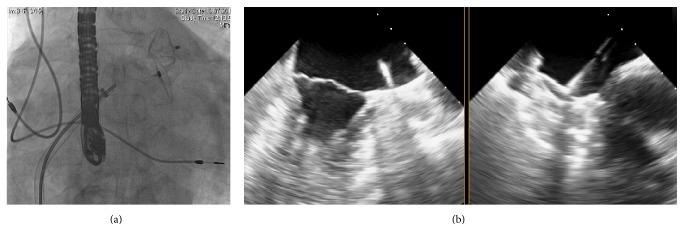

The Amplatzer Cardiac Plug (ACP) is one of the most commonly used devices for percutaneous left atrial appendage (LAA) closure in order to prevent a stroke in patients with atrial fibrillation and contraindication for long-term oral anticoagulation therapy. We have previously described a patient who had experienced an embolization of the ACP device about 12 months after implantation and the device could be percutaneously retrieved. A few years later, he suffered from a posterior stroke and a stroke located in the brainstem as well as a transischemic attack (TIA). In order to protect him from further cardioembolic events a reocclusion of the LAA with the new generation of ACP device, the Amplatzer Amulet, was performed. A stable position of the device within follow-up period could be confirmed and the patient was free of additional strokes/TIA or bleeding events. This case stresses the importance of proper LAA sizing in order to prevent device embolization and notes that LAA size is not static. Moreover, it demonstrates that repeated implantation of an LAA occlusion device was still possible; one should be aware of undersizing the LAA dimensions and that the modifications of new generation LAA occlusion devices may overcome limitations of first-generation devices in order to prevent a cardioembolic stroke.

https://cdn.ncbi.nlm.nih.gov/pmc/blobs/5d88/5075287/4dde0b04951b/CRIC2016-8438923.001.jpg